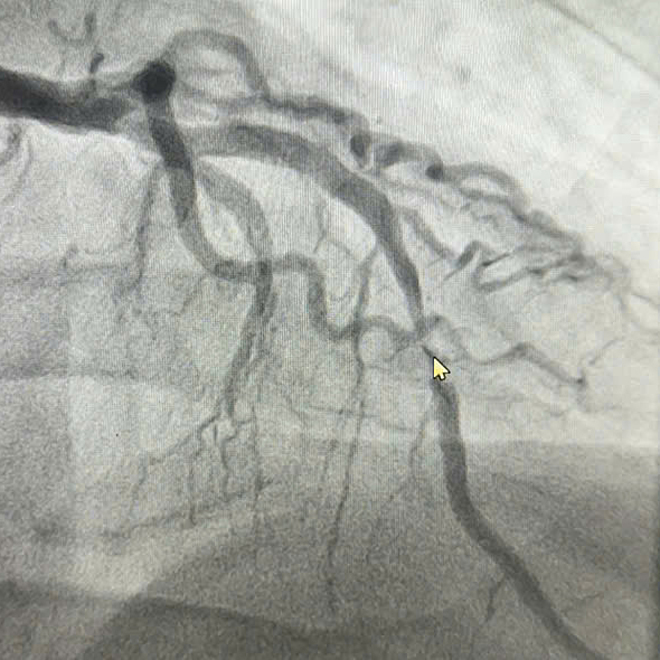

Hình ảnh động mạch hẹp trước khi can thiệp. Ảnh: Bệnh viện cung cấp

Ngày 5/11,đại diện Bệnh viện Đa khoa Hùng Vương cho biết người bệnh tiền sử tăng huyết áp,có thói quen hút thuốc lá để giảm căng thẳng. Khi vào viện,bệnh nhân đau ngực dữ dội. Từ kết quả điện tim và triệu chứng lâm sàng,bác sĩ chẩn đoán nhồi máu cơ tim cấp,động mạch liên thất trước (LAD) bị hẹp tới 99% do huyết khối.

Nhận định tình trạng khẩn cấp,êkíp can thiệp đặt một stent phủ kín vùng tổn thương để dòng chảy qua động mạch vành của bệnh nhân tái thông. Sau can thiệp,tình trạng đau ngực giảm rõ rệt.